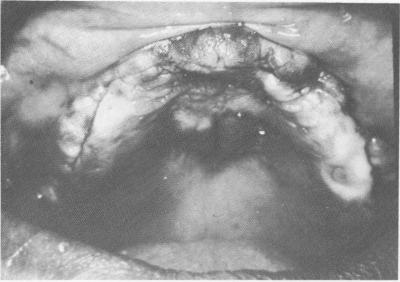

At the next visit the tissues were again incised and reflected to insert the implant (Fig. 11-191). The tissues were sutured over the implant (Fig. 11-192). When the tissues had nearly healed (Fig. 11-193),

Fig. 11-188. An elastic impression was made including ex-posed palate and the posterior grooves.